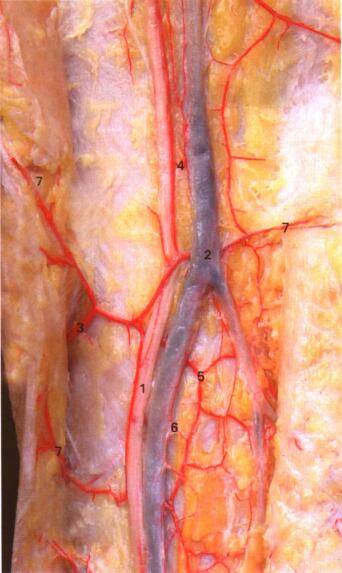

股薄肌皮瓣

股薄肌起于耻骨及坐骨下支

经股骨内髁后方,缝匠肌深面,止于胫骨粗隆内侧面